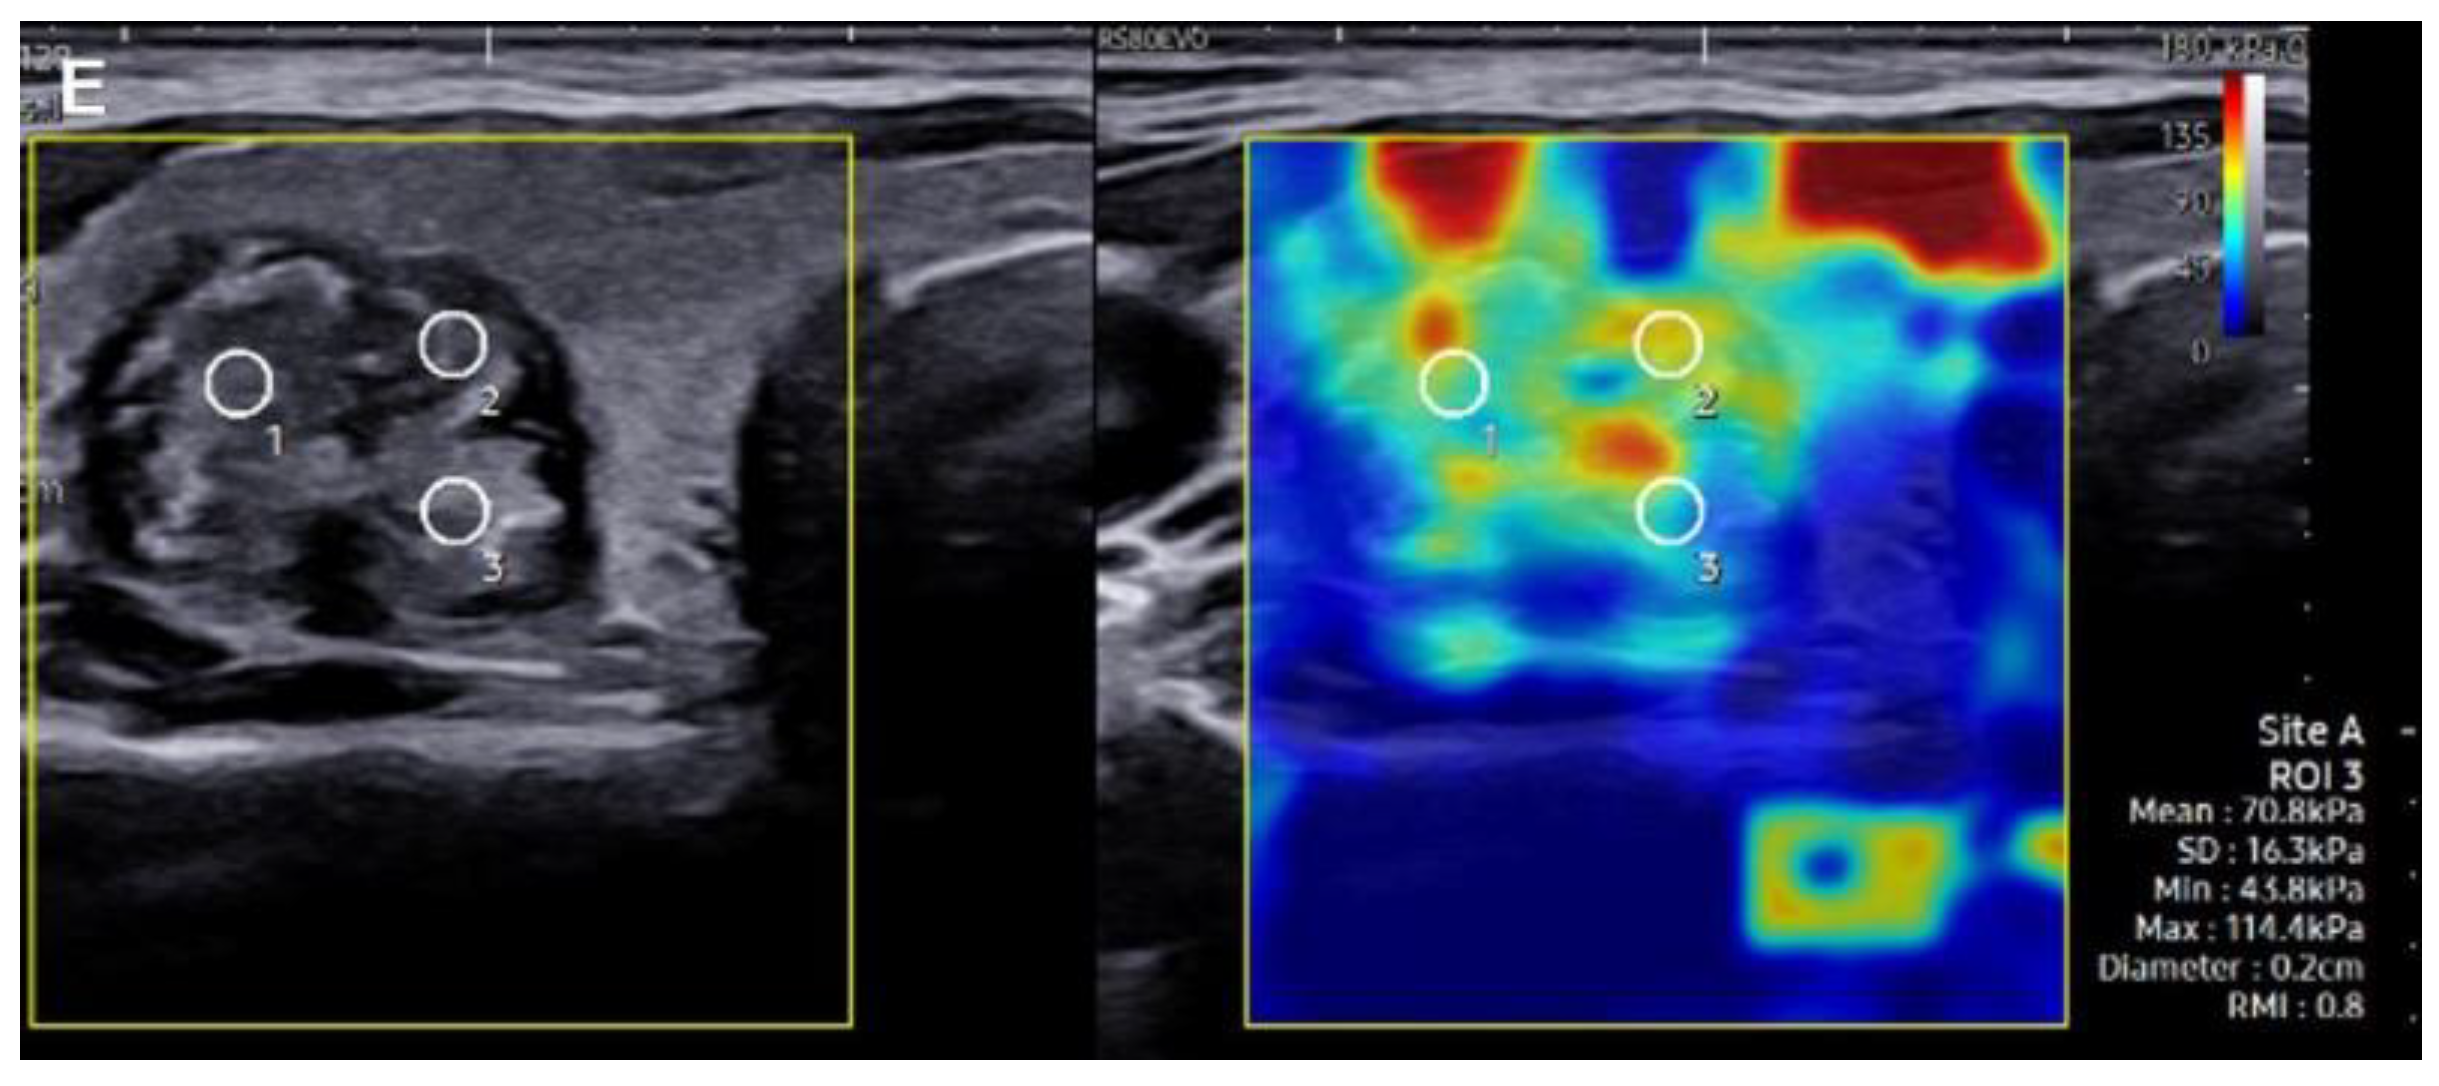

2.2. SWE Evaluation and Measurement